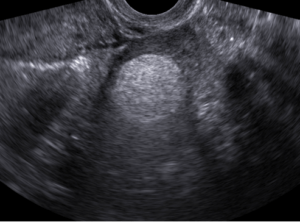

O diagnóstico do teratoma no ovário pode ser realizado sem dificuldades pelo ultrassom transvaginal.

Quando existir alguma dúvida quanto ao diagnóstico está indicada a ressonância magnética, mas na maior parte das vezes não é necessário.